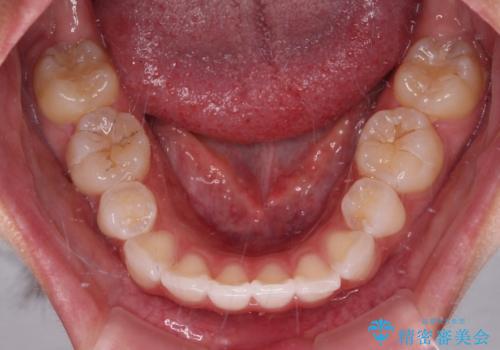

- 上下前歯の叢生を気にして来院された患者様です。

インビザラインでの治療を希望されていて、デコボコの程度が中等度であり、安価なパッケージにて対応可能と判断されたため、インビザライン・モデレートを用いて矯正治療を行うこととしました。